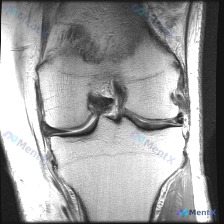

看到这份膝关节MRI的病例,整理一下读片思路分享给大家。 病例基本影像信息 本次仅提供膝关节MRI T1序列冠状位单张图像,提示问题为"半月板异常",整理读片所见如下: 1. 骨骼结构:股骨远端、胫骨近端骨皮质连续,无骨折,骨髓腔内信号均匀,无异常信号灶 2. 半月板情况:外侧半月板形态信号基本正常...